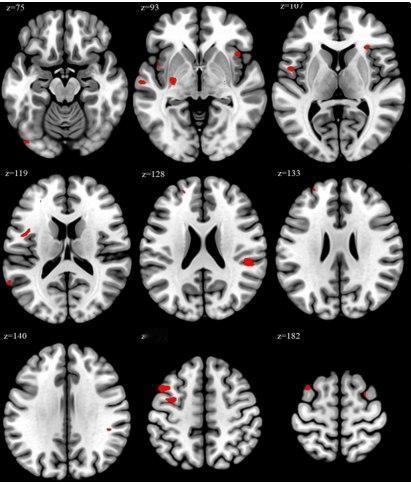

996伤脑?研究发现:长时间工作竟会改变大脑结构! 一项发表于《职业与环境医学》的研究一项最新研究显示,长时间工作可能导致大脑结构发生变化。研究人员对比了 overworked(每周工作≥52小时)和 non-overworked 两组医护人员的大脑结构,发现 overworked 组在与执行功能和情绪调节相关的大脑区域,如额中回、脑岛等,脑容量显著增加。 这表明,长时间工作可能引起大脑的适应性改变。 研究还发现,工作时长与这些脑区的容量变化存在正相关。 换句话说,工作时间越长,这些区域的脑容量增加越多。 这一结果为长时间工作对认知和情绪健康的潜在神经生物学影响提供了新的证据。 尽管研究人员认为这可能是大脑的一种适应性反应,但长期影响仍需进一步研究。 毕竟,大脑的改变是好是坏,现在下结论还为时过早。